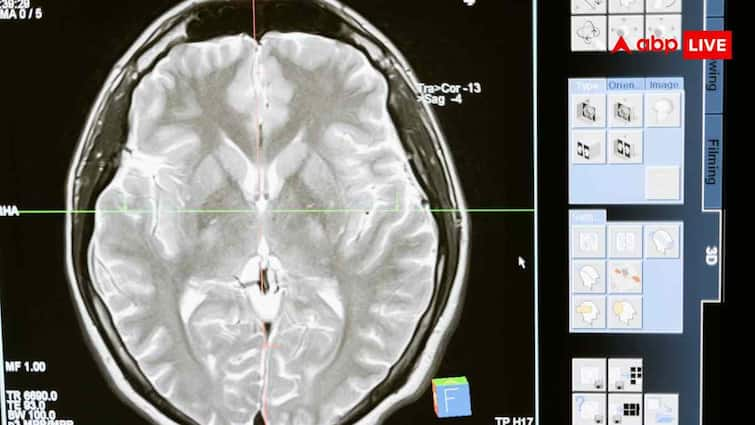

Till now we have believed that memory is only a function of the brain. But now a new research has completely changed this thinking. A special study by New York University scientist Dr. Nikolai Kukushkin has made a shocking claim that our memory is not limited to the brain only, but memory-like processes also occur in the cells of the kidney, skin and other organs.

This research has been published in the famous scientific journal Nature Communication. It has been told that the non-neural cells of our body, such as kidney cells, also have the ability to remember some information, just like neurons do. So let us know what is the shocking claim in the research.